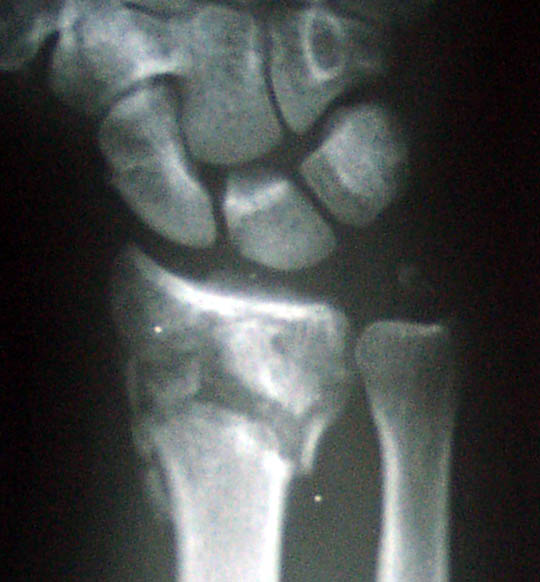

| Here are before and after xrays. Note that there is now more space between the arm bones and the wrist bones. | |

Before | After |

In fact, the doc thought there was a bit too much space so he decided to move the gadget screwed into my wrist back on the bar a millimeter or so. To do this, he used a cute gadget that clamps onto the rod and then provides a screw adjustment, one mm per turn. |

There is a chunk of displaced bone on the end of the raduis on the palm side. The surgeon decided to leave it alone to minimize the amount of cutting he did. I hope it doesn't give me trouble in the future. |